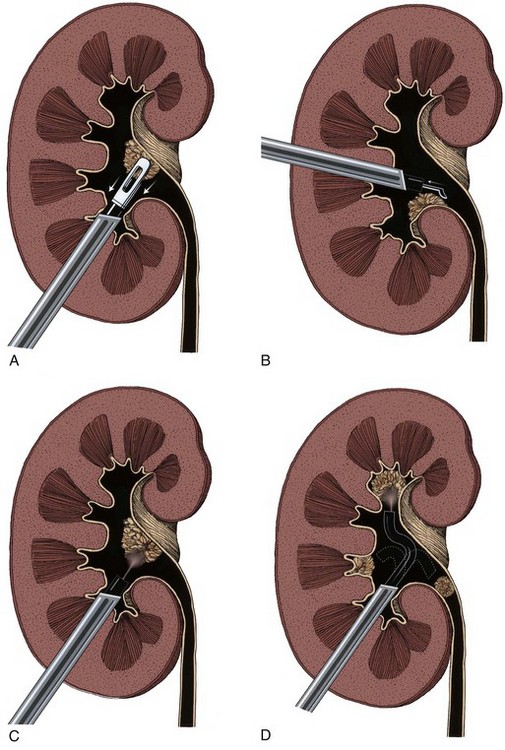

The treatment of upper tract urothelial tumors has undergone significant changes. The relatively low frequency of these lesions and the lack of prospective randomized trials do not permit absolute conclusions about treatment impact on outcomes. In the past, treatment recommendations were based, at least in part, on practical limitations in follow-up and detection of local disease recurrence. Technologic improvements in imaging and, most important, direct endoscopic visualization of all levels of the urinary tract allow earlier and more accurate initial diagnosis and treatment and improved follow-up. Treatment may be based primarily on the risk the tumor poses and on the efficacy of a specific treatment rather than on other considerations. The specific indications and techniques for each form of treatment (open vs. laparoscopic radical nephroureterectomy; open vs. retrograde endoscopic vs. percutaneous renal-sparing tumor ablation) are addressed later in this chapter. However, the following introductory considerations apply.

The least invasive and least ablative treatment necessary for safe control of the tumor is preferred. Most upper tract urothelial tumors are not large or bulky. Thus, laparoscopic surgery is ideal, at least for the renal portion of radical nephroureterectomy when the tumor warrants removal of the entire renal unit (see later). A variety of approaches with various combinations of laparoscopic and open techniques are employed for distal ureterectomy. Low-grade noninvasive upper tract tumors are managed initially by ablative renal-sparing surgery. Retrograde ureteroscopy and ureteropyeloscopy are preferred when tumor size, number, and access allow complete tumor ablation. Percutaneous antegrade tumor ablation is chosen when the anatomy and the tumor do not allow complete ablation through a retrograde approach.

Open conservative surgery may be applied in selected cases when nephron sparing for preservation of renal function is required (Gittes, 1966, 1980; Petkovic, 1972a, 1972b; Mazeman, 1976; Johnson and Babaian, 1979; Babaian and Johnson, 1980; Cummings, 1980; Wallace et al, 1981; Tomera et al, 1982; McCarron et al, 1983; Zincke and Neves, 1984; Bazeed et al, 1986; Ziegelbaum et al, 1987; Messing and Catalona, 1998). Tumor in a solitary kidney, synchronous bilateral tumors, and predisposition to form multiple recurrences, as in endemic Balkan nephropathy, are all reasons to consider nephron sparing (Fig. 53–6). Pyeloscopy as an initial diagnostic component to open conservative surgery has been supplanted by retrograde or percutaneous antegrade renal endoscopy (Huffman et al, 1985). Direct endoscopic visualization of the lesion and biopsy with cup forceps or brush establish a definitive diagnosis and tumor grade (Gill et al, 1973). The brush biopsy has renewed value because tissue obtained by small cup biopsy forceps used through narrow-caliber flexible endoscopes is limited. Preoperative determination of the stage of renal pelvis tumors remains difficult. Large size, broad base, and nonpapillary pattern favor tumor invasiveness. These improvements in initial diagnosis and assessment of tumor stage and grade allow more specific treatment, including conservative surgery when it is indicated.

The documented risk of wound implantation by tumor is low after open conservative surgery if simple precautions are followed to minimize spillage (Gittes, 1980; Tomera et al, 1982; McCarron et al, 1983). Modern percutaneous antegrade renal surgery allows resection of virtually any lesion formerly treated by open pyeloscopy, and the risk of tumor spillage is even lower (see following discussion).

The patient is placed in either a full flank or a torque position, as shown in Chapter 54. The full flank position provides optimal exposure to the renal pelvis for pyelotomy and excision of a large noninvasive tumor. The torque position allows both anterior and posterior exposure to the renal pedicle for partial nephrectomy. An extrapleural, extraperitoneal flank, or thoracoabdominal incision is made. Removal of a portion of the 11th or 12th rib provides maximal exposure to the kidney and aids in mobilization of the upper pole and in gaining access to the renal vessels. Removal of a rib is especially helpful in obese patients or in those with a high kidney. An incision off the tip of the 12th rib suffices in thin patients with a low kidney and is accompanied by less potential wound discomfort or morbidity. After the incision is completed, the Gerota fascia is opened posteriorly and the entire kidney is mobilized. The renal vessels and the ureter are each isolated with a vessel loop.

The wound is packed with dry sponges to isolate the kidney before any intrarenal incisions are made. For pyelotomy and tumor excision the renal pelvis and the major calyceal infundibula are exposed by dissecting the hilar and renal sinus fat as for an extended pyelolithotomy. A gentle curvilinear incision is made in the renal pelvis, and the tumor is excised; the base is cauterized with electrocautery, laser, or argon beam coagulator. Finally, the pelvis is closed with 4-0 chromic catgut or other absorbable suture.

The techniques of partial nephrectomy for renal pelvis tumors are essentially the same as those described in Chapter 54, with the added proviso of taking care to minimize the risk of tumor spillage. The involved segment of the intrarenal collecting system is clamped before removal of the tumor-bearing portion of the kidney is begun. The collecting system of the renal remnant is closed with absorbable 4-0 suture. Identified individual bleeding points are oversewn with 4-0 vascular Prolene or polydioxanone suture. Additional hemostasis is provided by use of electrocautery and the argon beam coagulator on the raw parenchymal surface. The edges of the renal defect and the adjoining renal capsule are approximated over Surgicel bolsters with 2-0 chromic catgut suture.

A suction drain is placed in the renal bed in all cases. A temporary urinary diversion stent is not used routinely unless difficulty is encountered in closing the collecting system.